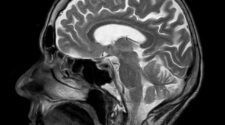

Mágneses rezonancia (MR)

Az MR vizsgálat az úgynevezett mágnesen magrezonancián alapszik. Lényege, hogy a vizsgálat során egy mágneses térbe kerülünk, ahol különböző irányokból képeket készít rólunk a radiológus. MR-t szokás alkalmazni a rendszeres fejfájások, szédülések kivizsgálására, de a gerinc állapotát is jól fel lehet mérni vele. Mindemellett pedig a hasi szervek, emlők, illetve a nyirokcsomók vizsgálatában is nagy segítséget nyújt.